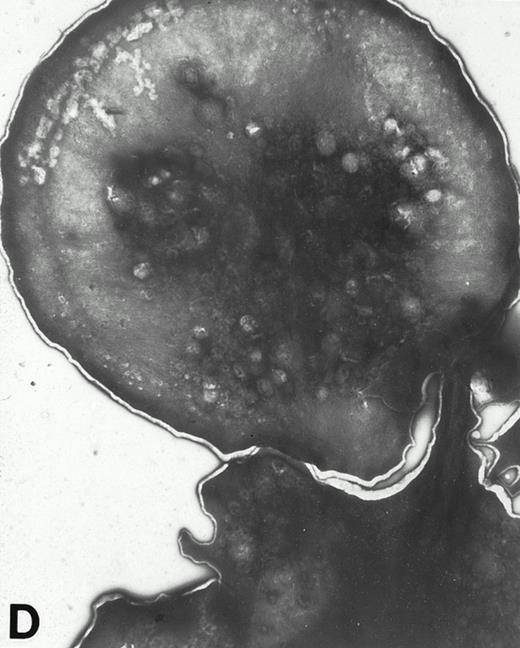

Wistar rat platelets allowed to adhere for 30 seconds (A) or 1 minute (B) onto Formvar-coated, carbon-stabilized grids, and subsequently fixed and stained with uranyl acetate. WF rat platelets allowed to adhere for 30 seconds (C) or 1 minute (D) onto Formvar-coated, carbon-stabilized grids. (A through D, original magnification ×3,700).

(A) Representative resting WF rat platelets prepared identically to resting Wistar platelets in Fig 2. (B through E) WF rat platelets allowed to adhere to Formvar-coated, carbon-stabilized grids from 30 seconds to 30 minutes, and subsequently fixed and stained with uranyl acetate. (B through E) illustrate the forms characteristic of WF rat platelet spreading, including platelets with stubby filopodia (B), lamellipodia (C), or fully spread forms (D and E). (E) shows the spread margin of a WF platelet at higher power. The arrowheads indicate microtubules and the asterisk shows the dense peripheral weave at the platelet margin. (B) 30-second adherent sample, (C) 1-minute adherent sample, (D and E) 30-minute adherent sample. (A through D, original magnification ×7,000; E, original magnification ×19,000).